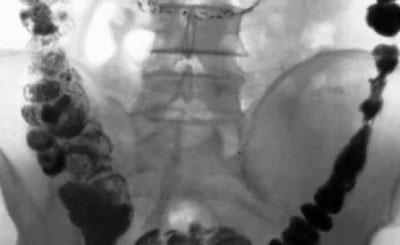

Из-за неправильного питания в кишечнике откладываются шлаки и каловые камни, которые препятствуют эффективному всасыванию полезных веществ. Это происходит вследствие многолетнего употребления жирного, жареного, соленого и копченого. Алкоголь и курение тоже оставляют свой след. Если планируется похудеть и оздоровиться, то от пагубных пристрастий лучше отказаться.

Отложения на стенках кишечника – это первое, от чего необходимо избавиться. Когда они уйдут, организм примется эффективно расходовать накопленный жир. Поэтому основная цель подготовительной очистительной диеты – освобождение ЖКТ от всего лишнего и чужеродного.

Очищение организма в домашних условиях Для очистки кишечника применяют клизмы с соленой водой, отвары лекарственных трав, отруби, свежие овощи, кефир и свежевыжатые соки. В медицинских учреждениях с этой целью используют мониторную очистку кишечника от каловых камней.